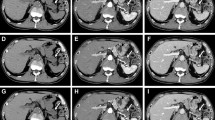

Our institutional review board approved this prospective study. Written informed consent was obtained from all patients. Twenty-eight consecutive patients with PDAC undergoing chemotherapy (14 men and 14 women; mean age, 68.4 years) underwent pancreatic LDCT for therapy evaluation. The LDCT images were reconstructed using 40% adaptive statistical iterative reconstruction-Veo (hybrid-IR) and DLIR at medium and high levels (DLIR-M and DLIR-H). The image noise, diagnostic acceptability, and conspicuity of PDAC were qualitatively assessed using a 5-point scale. CT numbers of the abdominal aorta, portal vein, pancreas, PDAC, background noise, signal-to-noise ratio (SNR) of the anatomical structures, and tumor-to-pancreas contrast-to-noise ratio (CNR) were calculated. Qualitative and quantitative parameters were compared between the hybrid-IR, DLIR-M, and DLIR-H images.

CT dose-index volumes and dose-length product in pancreatic LDCT were 2.3 ± 1.0 mGy and 74.9 ± 37.0 mGy•cm, respectively. The image noise, diagnostic acceptability, and conspicuity of PDAC were significantly better in DLIR-H than those in hybrid-IR and DLIR-M (all P < 0.001). The background noise was significantly lower in the DLIR-H images (P < 0.001) and resulted in improved SNRs (P < 0.001) and CNR (P < 0.001) compared with those in the hybrid-IR and DLIR-M images.

DLIR significantly reduced image noise and improved image quality in pancreatic LDCT images compared with hybrid-IR.